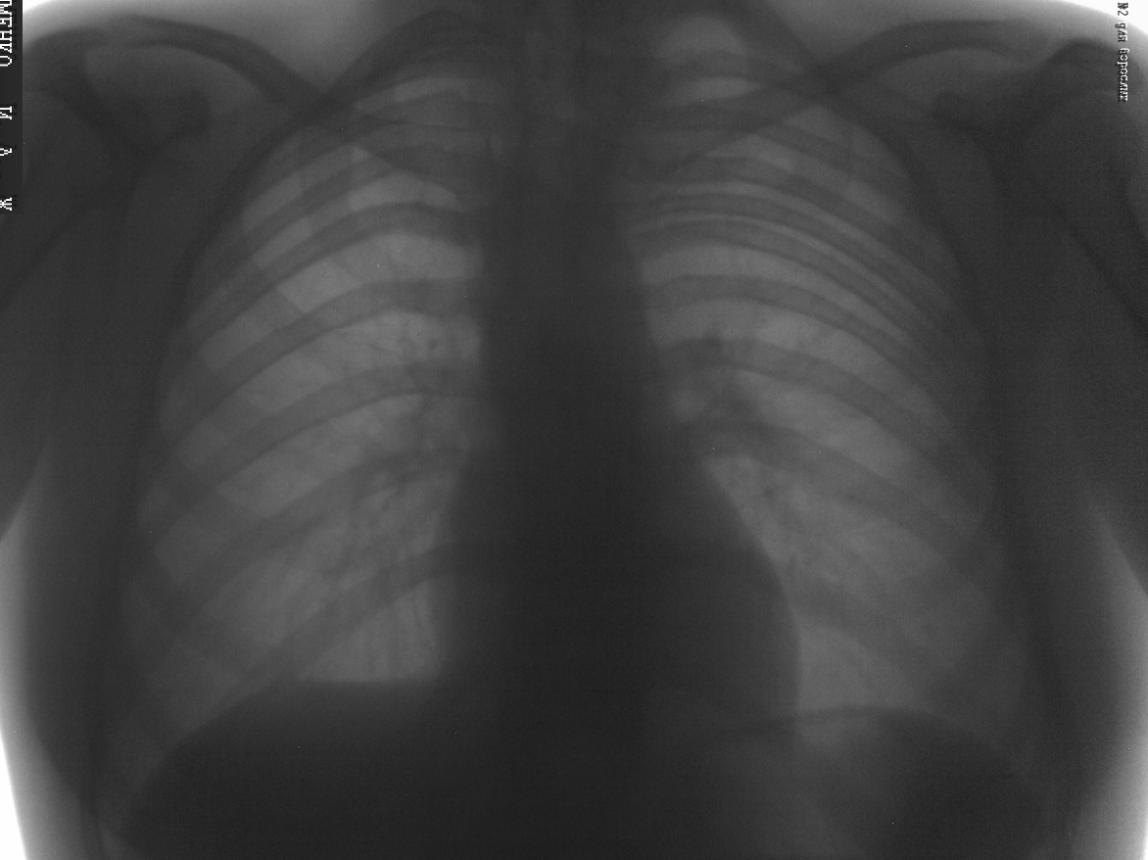

День добрый уважаемые коллеги. Прошу оценить качество выполненной "флюшки". (Флюшка не обрабатывалась. В чем причина такой "зашумленности" изображения?). Всем заранее спасибо за ответы.

Андрей Юрьевич! А как Вам добавочное ребро слева? А вопросы Вы правильные поставили. Мне лично, видиться серый малоконтрастный снимок за счет перебора киловольт.

Спасибо за замечания. Скажу что помню : Аппарат "Индиарс - 12ф7 с цифровой обработкой изображения" Разрешающая способность 2 пар лин. (На счет режимов съемки: 70 кв 0.05мс ). Завтра выложу прямые проекции и боковые.

Снимок показался интересным из-зане часто встречающейся локализации добавочного ребра

ВОПРОС был и есть "В чем причина такой "зашумленности" изображения?".

Дело в том что все снимки на флюорографе "шумят" одни больше другие меньше. Хотелось бы узнать так должно быть? Снимок нормы выставлять не хотелось, хотел выставить что-то поинтереснее. Если что то не так прошу извинить.

Пункт второй: но улучшить можно. Для начала увеличьте киловольтаж, 70 кВ - это мало. У меня меньше 80 вообще не ставят. Если аппарат еще на гарантии, то приглашайте представителй, пусть налаживают.

Для уменьшения шума, первое средство - увеличение экспозиции, представленный снимок кажется мне недоэкспонирорванным. Устройство аппарата надо знать, какой приемник (размеры в см, пикселях)? Не совсем понятен режим съемки: "70 кв 0.05мс", вероятно ошибка, не 0.05 мс, а 50 мс, т.е. 0.05 сек? 70 кв для однофазного, двухполупериодного питающего устройства, ИМХО, недостаточно, мы такое напряжение ставим только на дистрофиков..